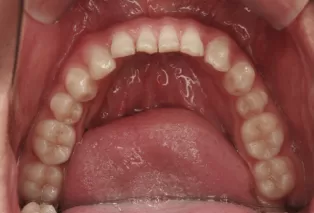

Intraoral photos